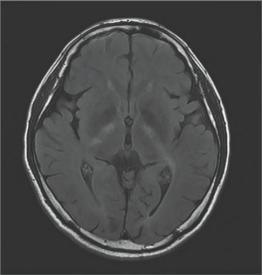

颅脑MRI提示双侧内囊膝、双侧内囊后肢、双侧大脑脚、脑桥和小脑齿状核处有对称的异常信号:

这一看,显然是脑袋出了问题呀。患者的性格变化跟这个脱不了关系。

据报道,颅脑MRI中出现小脑齿状核异常信号可能是CTX的特异性表现。